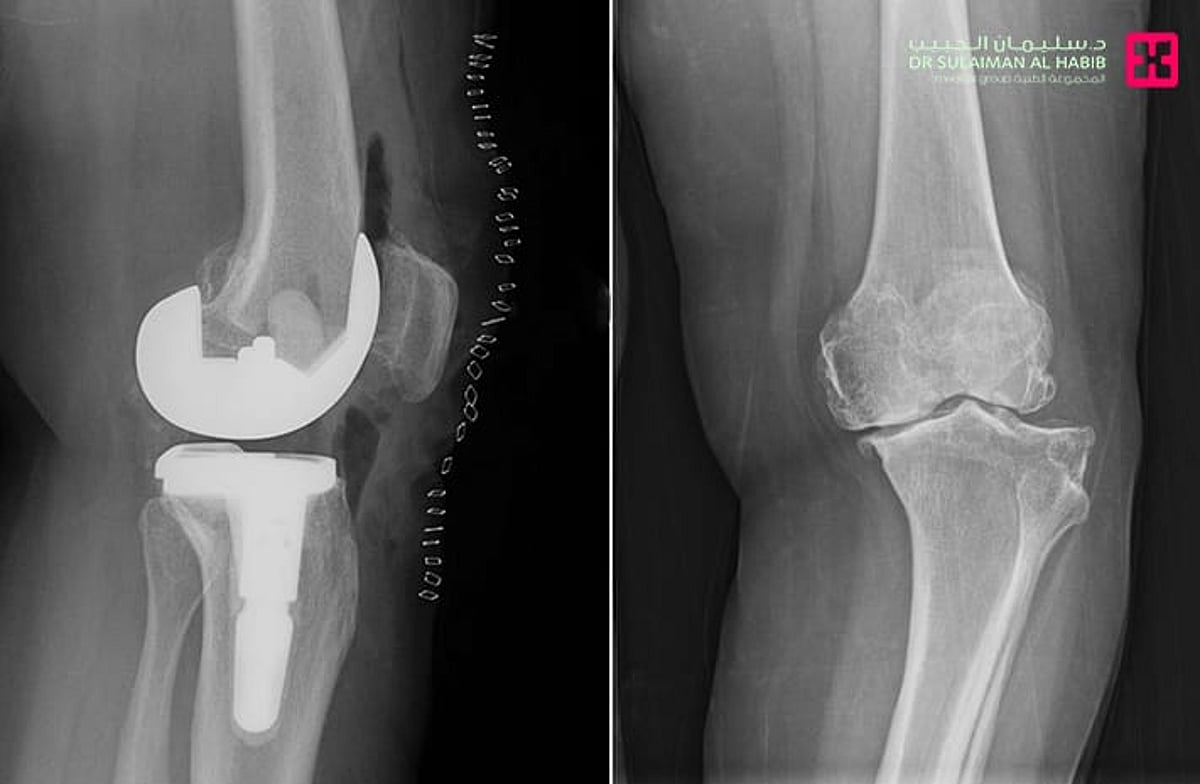

مستشفى الدكتور سليمان الحبيب بالقصيم ينهي معاناة “ستينية” بعملية استبدال مفصل ركبة نوعية

نجح مستشفى الدكتور سليمان الحبيب بالقصيم في إجراء عملية نوعية ناجحة لاستبدال مفصل الركبة اليسرى بتقنية حديثة تُخفّف الآلام وتُسرّع التعافي، منهيةً معاناة سيدة ستينية كانت تعاني من خشونة شديدة واحتكاك حاد وتلف في غضاريف المفصل.